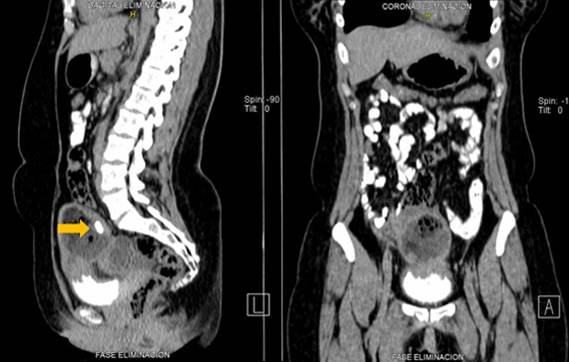

La tomografía axial computarizada (TAC) abdomino pélvica con doble contraste reportó, lesión ocupante de espacio (LOE) parauterina derecha, densidad heterogénea de 7,5 x 6,1 cm, con presencia de imágenes de densidad grasa, densidad de partes blandas y una imagen calcificada en su interior (Figura 3). Además, reportó LOE a nivel anexial izquierdo de aspecto quístico, de rango líquido, tabicada, con paredes delgadas, tamaño aproximado 5,7 x 4,8 cm (Figura 4).

Figura 3 Tomografía axial computarizada en corte sagital y coronal donde muestra lesión ocupante de espacio parauterina derecha, con presencia de imágenes de densidad grasa, densidad de partes blandas y una imagen calcificada en su interior (flecha).